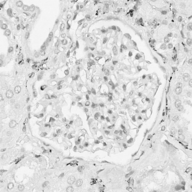

Image datasets in digital pathology applications often consist of consecutive slides stained differently, each staining providing specific information on the same region of interest (see Figure 1, first row). Even though differently stained slides appear very different, there is often a significant amount of consistent information between them. For example, they may both share the same counterstain (e.g. haematoxylin), or they may highlight different parts of the same structure.

The analysis and integration of information from different stainings is usually performed with reference to a specific organ, structure, or pattern observed in the tissue. For example, to diagnose pathologies such as breast cancer or kidney allograft rejection it is necessary to study the inflammatory micro-environment of the organ. In these cases, the relevant information is the distribution of immune cells (e.g. macrophages or lymphocytes) in relation to important structures of the organ, such as glomeruli for the kidney, or lobules for the breast.

Objects to be segmented, e.g. glomeruli, are generally easily identified between stainings as globally they exhibit the same structure and texture, see Figure 1. It should therefore be possible to bias the network to learn stain invariant features. This work investigates this possibility by modifying the data presented to the network in an unsupervised manner. Borrowing domain adaptation terminology, herein the staining used for training and validation is referred to as as the source staining (irrespective of any transformations), and the stainings to which the network are applied as target stainings.

N.B. the intention is to present plausible colour profiles to the network. This does not necessarily correspond to biologically relevant image information but is explored for any potential for the tested staining modalities. Potential limitations are addressed, e.g. in Figure 1 the bright red colour (chromogenic reaction used to detect CD34, a marker of blood vessel inner lining) could be successfully transferred but it is not localised as in the original image.

Next is a strategy to extract biological information that is consistent across different stainings—the haematoxylin counterstain. Despite this biological plausibility, it does not result in good results. Indeed, the haematoxylin transformed images vary greatly between the different stainings (see Figure 1, second row). Several factors may explain this: 1) haematoxylin’s concentration relative to the primary stain may vary from one staining to another, resulting in different shades of blue and fixation amount; 2) as a counterstain, haematoxylin may become mixed with another stain in structures that are targeted by both. These result in a color mixing that is in practice not perfectly unmixed by a color deconvolution algorithm.